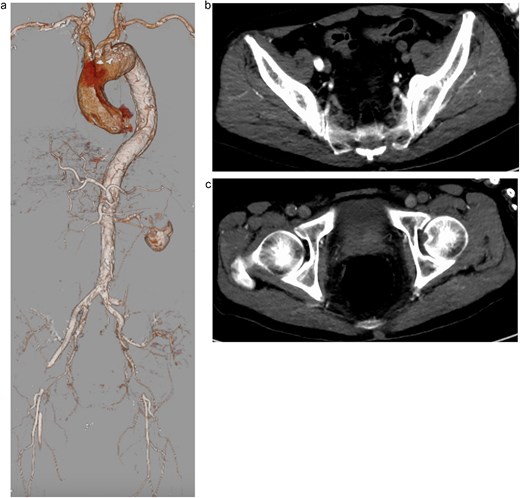

A 74-year-old man with a history of hypertension, chronic kidney disease, and a distal aortic arch aneurysm presented with sudden-onset bilateral leg weakness and sensory loss. On admission, femoral, popliteal, and pedal pulses were absent bilaterally. Contrast-enhanced computed tomography (CT) revealed AADA with a saccular aneurysm in the distal aortic arch and severe true lumen narrowing at the abdominal aorta, resulting in right renal and lower limb malperfusion (Fig. 1a–c).

Preoperative contrast-enhanced computed tomography (CT) showing severe narrowing of the true lumen at the abdominal aorta, with dynamic obstruction of both renal arteries and static obstruction of the left external iliac and right common femoral arteries. (a) Three-dimensional reconstruction, (b) axial CT image at the level of iliac arteries, and (c) axial CT image at the level of femoral arteries.